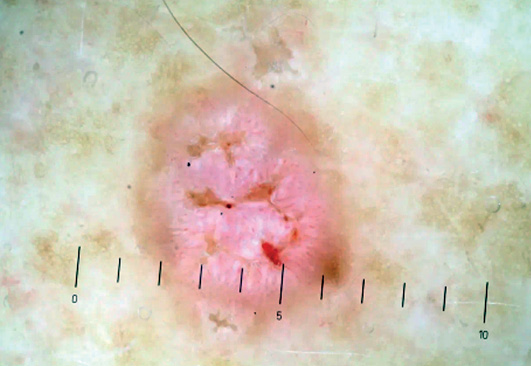

Дерматоскопические изображения для последующего анализа были получены с помощью дерматоскопов DermLite DL3N, Heine DELTA 20(T), адаптеров и фотоаппаратов Nikon 1 J1, Canon 750D. Фотографии сделаны в поляризованном режиме дерматоскопа с использованием ультразвукового геля в качестве иммерсии.

- 10 пациентов с единичными кератоакантомами, диагноз во всех случаях подтвержден патоморфологическим исследованием;

- 24 пациента с ПКРК, диагноз во всех случаях подтвержден патоморфологическим исследованием.